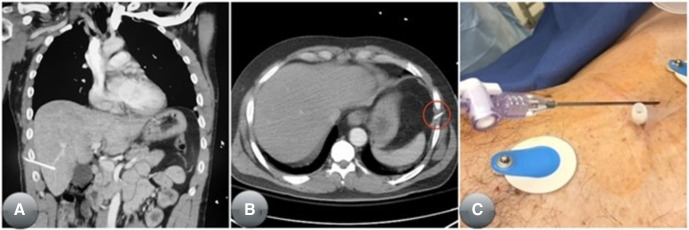

최종적으로 포함된 84명의 환자 중 대다수는 남성이었으며(n=78, 92.9%), 둔상 외상을 입었고(n=58, 69.1%), TT을 시행받았으며(n=68, 81%), 육상 후송으로 도착했다(n=48, 57.1%). 평균 연령은 38.6세(SD=16.04), 평균 BMI는 29.1kg/m²(SD=5.36), 평균 ISS는 28.69(SD=10.69)였다. 흉막강 내에 적절하게 NT가 삽입된 경우는 27.4%(n=23)에 불과했다. 전체 환자 중 단지 81.0%(n=64)만이 이후 흉관삽관술을 필요로 했다. NT 시도 과정에서 5명의 환자에서 의료행위로 인한 손상이 발생했다. 한 명은 비장에 삽입되었고, 두 명은 간에 삽입되었으며, 두 명은 횡격막하로 삽입되었고, 한 명은 전종격에 삽입되었다. 병원 재원 기간의 중앙값은 7일이었으며, ICU 재원 기간의 중앙값은 5일이었다. 전체 사망률은 15.5%(n=13)였다. 표 1은 이들 84명의 환자에 대한 세부 요약을 제시한다.

NT 삽입의 적절성 평가는, 특히 병원 전 단계 외상과 같이 역동적으로 변화하는 상황에서는 더욱 제한된다. 이번 연구에서 16명(22.5%)의 환자는 외상 소생술 시행 중 TT을 적용받지 않았는데, 이는 CT에서 기흉이나 혈흉이 발견되지 않았음을 의미한다. CT 소견에 따르면 이들 16명은 병원 전 단계에서 NT가 필요하지 않았던 것으로 보인다. 실제 비적응증 NT 시행률은 더 높을 수 있는데, 이는 NT가 시행된 이후 CT에서 발견된 기흉이 의료행위로 인해 발생한 것인지 여부를 판별할 수 없기 때문이다. NT는 적절한 적응증이 있는 경우에도 생명을 위협하는 출혈을 포함한 심각한 합병증을 초래할 수 있다 23. 또한 의료행위로 발생한 기흉에 대한 후속 TT는 환자를 간, 비장, 횡격막, 폐, 심장 손상 등 불필요한 합병증 위험에 노출시킨다 23. 본 연구에서도 NT의 부적절한 삽입으로 복강, 비장, 간에 발생한 의료행위 합병증 사례가 일부 관찰되었으며, 이는 그림 4에 제시되어 있다. 따라서 미국 전역의 EMS 규제 기관들은 의학적으로 불필요한 NT 시행을 최소화할 수 있는 전략을 모색해야 한다.